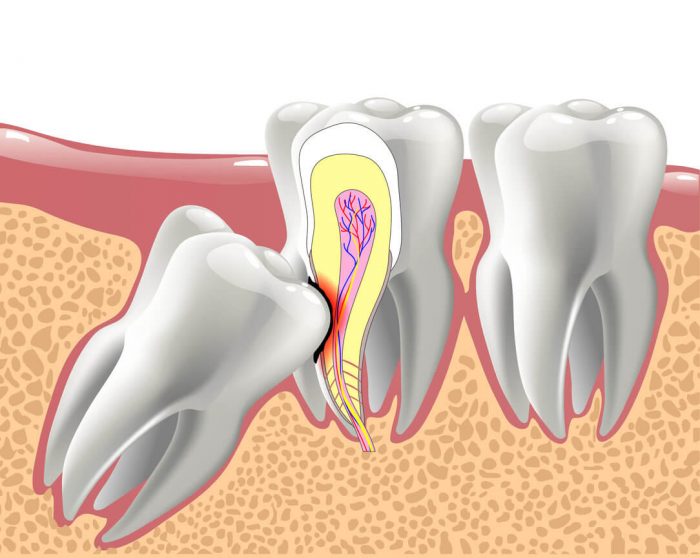

Wisdom tooth extraction is the removal of the four permanent molar teeth located at the top and bottom back corners of the mouth.we recommend that the wisdom teeth be removed early, preferably during the mid- to late teens, even if they haven’t begun to emerge from the gums yet.Call us for a free consultation at (281) 940-8940 or visit us At Edge Dental in Houston, TX.